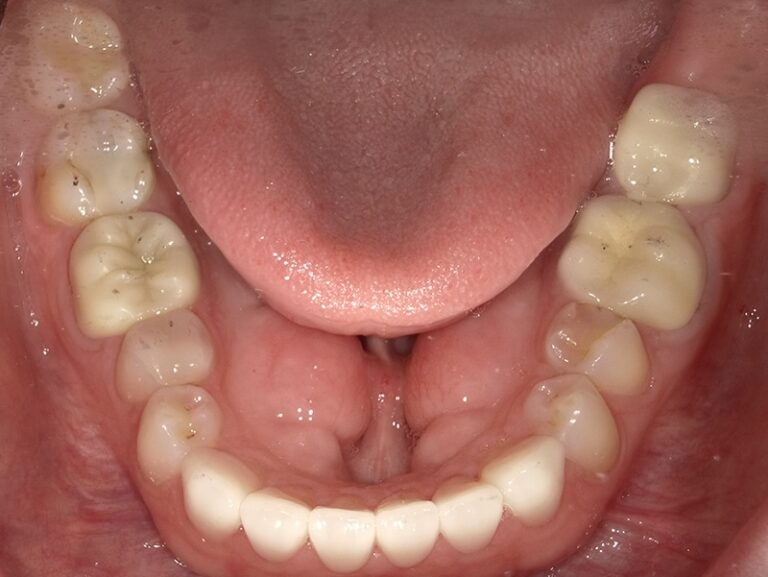

We began this patient's cosmetic journey with SureSmile clear aligners. We were able to accommodate patient's request of a shorter aligner treatment length, and move on to porcelain restorations. We placed 12 upper crowns and 6 lower veneers, thus giving her a beautiful new smile in a shorter timeframe!